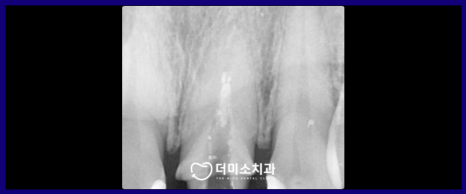

정밀한 검사를 위해

파노라마 사진과 X-ray 사진을

촬영해 보았더니

신경치료 후 채워 넣는 치과 재료가

뿌리 끝까지 꼼꼼하게 채워지지 않은

불완전 근관치료 상태인 것을

확인할 수 있었는데요.

이 경우 재신경치료가

필요한 상황이었습니다.